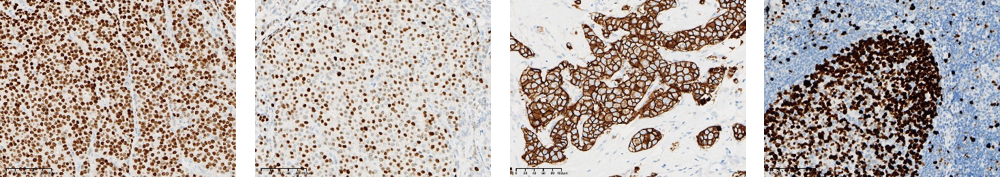

MLH1 | MSH2 | MSH6 | PMS2 |

ER | PR | HER2 | KI67 |

Claudin18.2 | CD20 | Bcl-2 | Bcl-6 |

C-MYC | 彈力纖維染色 | 粘液染色 | 剛果紅染色 |